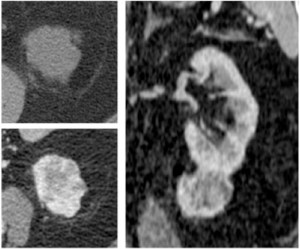

1. CARCINOMA DE CÉLULAS RENALES (CCR). (clíck para ver más)

Puede tener un crecimiento hacia la periferia, con invasión y rotura de la cápsula renal e infiltración del EPR, cuyo diagnóstico no siempre en posible con TC o RM. El tumor puede producir engrosamiento de la fascia perirrenal y de los septos, y espiculación en la grasa perirrenal. El tumor también puede extenderse como un bloque sólido en cualquier dirección sin afectar los septos del EPR.

Recordar que si en el seno de una masa encontramos densidad grasa, estamos ante un angiomiolipoma renal y no serían necesarios más estudios ni procedimiento invasivos como una nefrectomía.

3. METÁSTASIS.

Las más frecuente son por melanoma, carcinoma renal y carcinoma de pulmón.

Pueden asentar en el EPR dada su rica red vascular y linfática, frecuentemente sin afectación renal simultánea. El tumor primario renal puede tener una diseminación hacia el EPR por vía linfática o por los vasos capsulares renales.

Imagen en TC: nódulos de tamaño y densidad variables, con o sin contacto con el riñón.